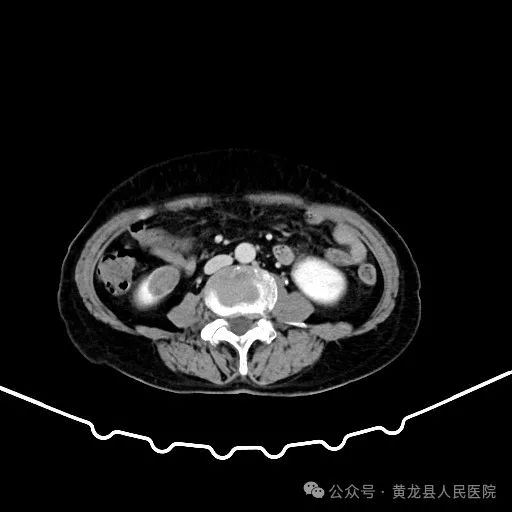

患者男性,70岁,因“发现右肾肿物1年余”收住于我院外科,经查体及相关检查后诊断为:右肾肿瘤。为尽早解除患者疾病困扰,方继荣主任迅速组织泌尿外科、手麻科、普外科等多学科进行会诊,对患者的病情进行了全面而深入的评估。最终确定详细周密手术方案,将患者病情及治疗方法告知患者及家属征得同意后,由我院泌尿外科刘涛主治医师实施手术。

双肾VR